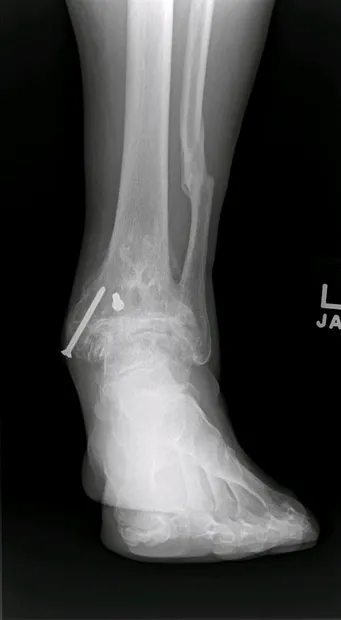

The following are images after surgical replacement of the ankle joint with a mobile bearing ankle prosthetic called the S.T.A.R. (SBI). This replacement joint will function similarly to a normal anatomical joint, allowing the patient normal function in daily activities, but was not designed to take repetitive use during more intense athletic activity. The joint has a polyethylene spacer between two metal parts that acts as shock absorber and gliding agent similar to cartilage. There is physical therapy that is required after surgical joint replacement in order to get the patient back to funcional capacity.

These are final pics of the ankle replacement after fusion takedown

Preop, Intraop and Postop X-rays status post Total Ankle Replacement for Ankle Arthritis